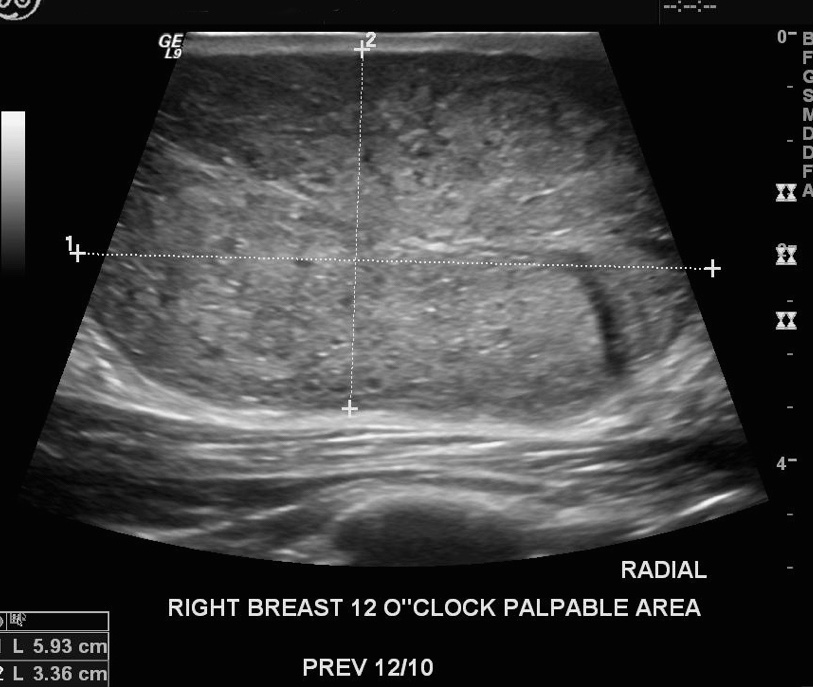

Ultrasound from 6-month follow-up

• The most recent ultrasound image shows:

• An isoechoic, heterogeneous mass that contains cystic, fluid filled spaces, and is vascular on Doppler examination

• Have margins that are well-circumscribed, and a thin, echogenic capsule is demonstrable

• Would in all likelihood have a less distinct border than the lesion shown above